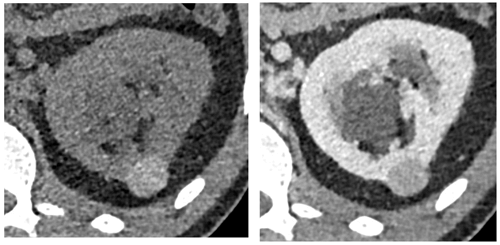

Papillary RCC is often hypointense on T2-weighted sequences and demonstrates low-level homogenous contrast enhancement (Figure 10). Clear cell RCC on the other hand appears hyperintense on T2-weighted sequences with intense heterogenous contrast enhancement and early wash-out.

Figure 10: Type I papillary RCC demonstrating quite low-level homogenous enhancement (left).

Bosniak IV cystic lesion within the contralateral kidney (right) also excised revealing papillary RCC.